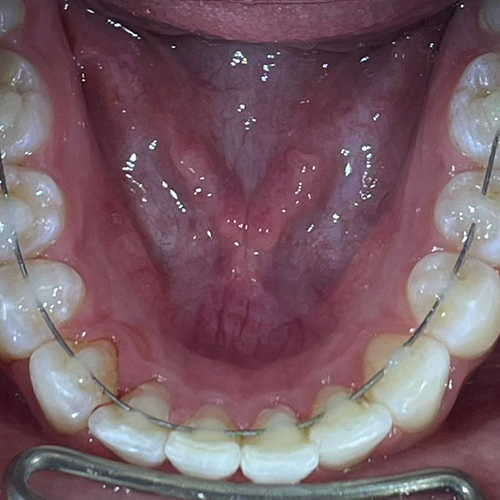

Comprueba en la práctica cómo el conocimiento se transforma en resultados reales a través de los casos de nuestros alumnos.

SALA DE PROCEDIMIENTOS

Siga clases prácticas y la evolución de casos clínicos reales directamente desde la clínica del Dr. Ary Nunes.